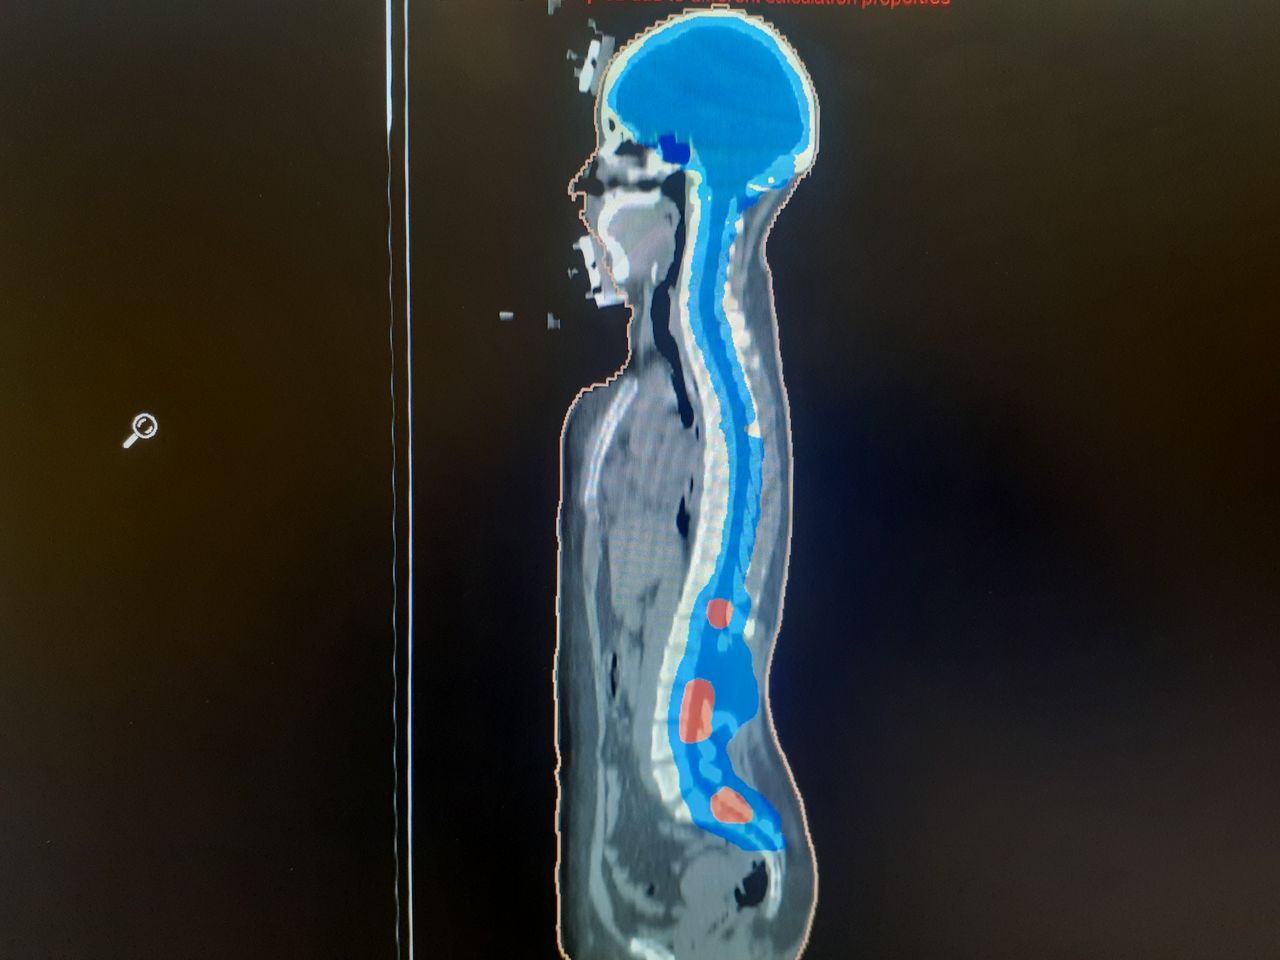

• Terapia de arco volumetrico modulado (VMAT)